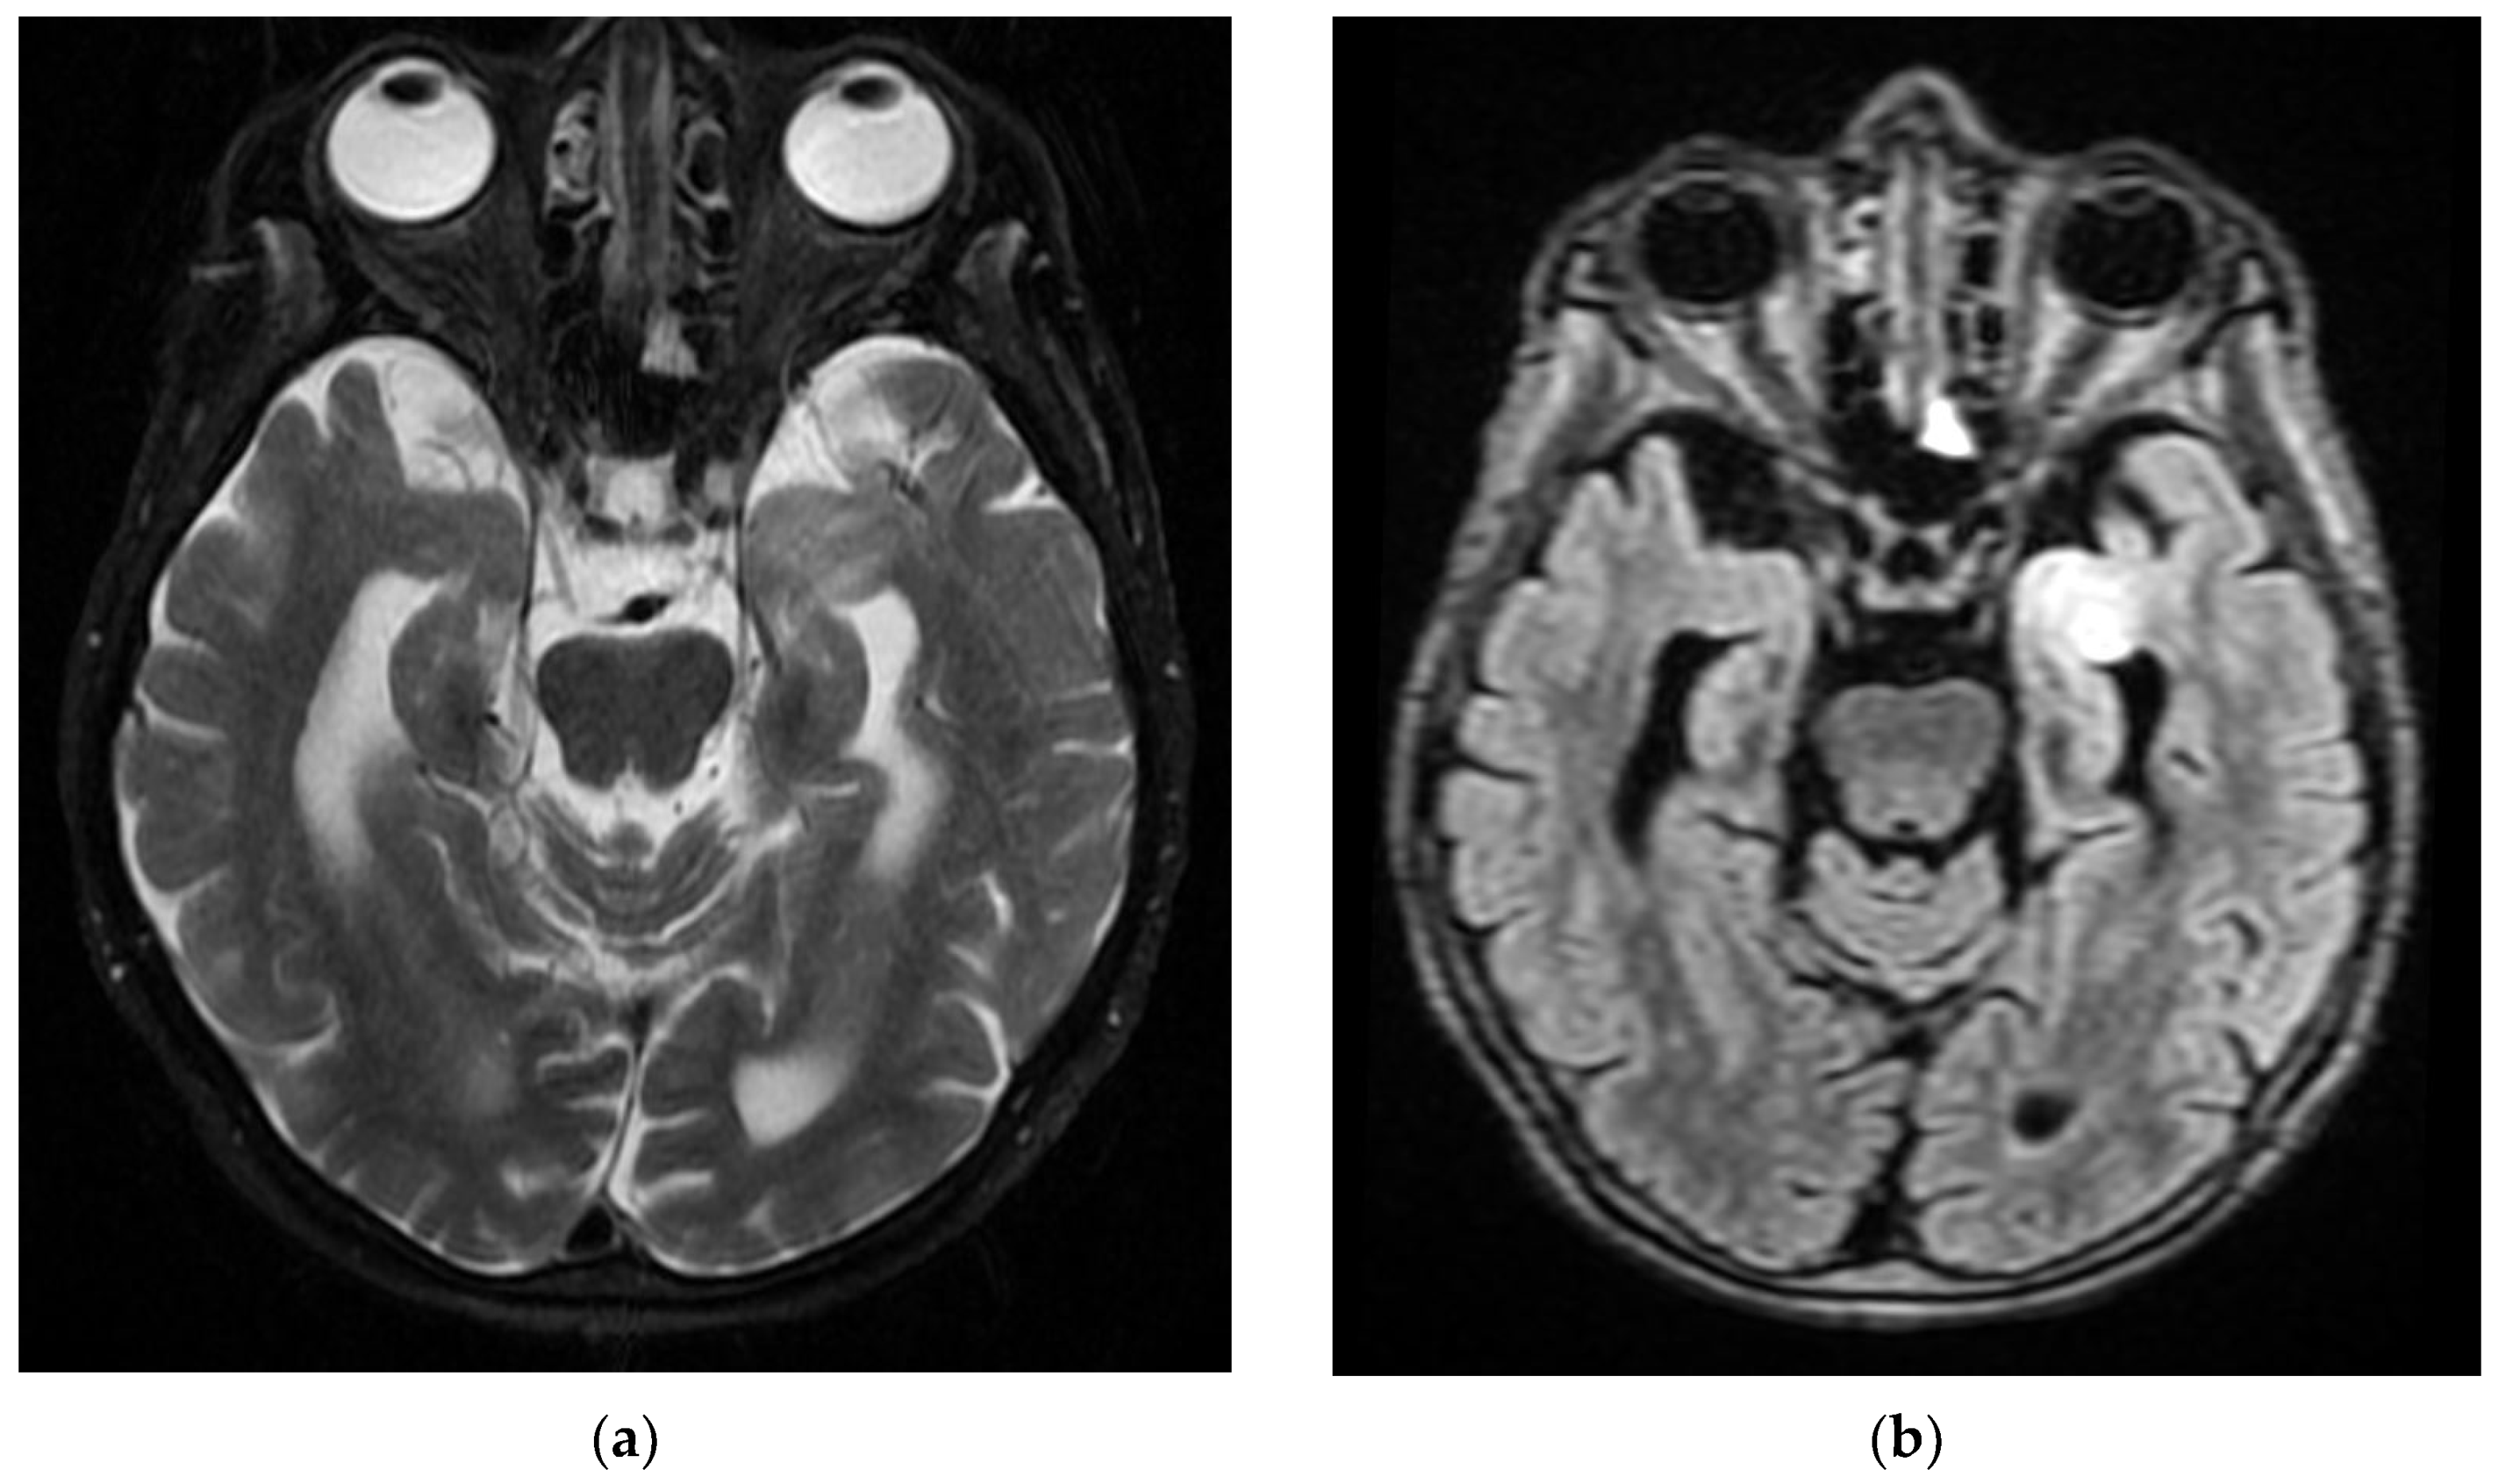

Figure 5. Cerebral MRI examination of the Case 5 patient highlights inaccurately delimited area of intense T2 and FLAIR signal (a,b), slightly restrictive in diffusion (c,d), situated in the cortical and subcortical area of the left tonsil. These images are conclusive for subacute tardive infarction on the territory of the anterior choroidal artery.

Chest CT angiography and PET were carried out for the pulmonary arteries and the native brain CT showed cerebellar abiotrophy. On day 5 of hospitalization, the brain CT was repeated, which showed an unchanged appearance from the previous CT examination (cerebellar abiotrophy; in observation, corpus callosum dysgenesis). On day 10 of hospitalization, a brain MRI was performed, which showed an imprecisely delimited area of intense T2/FLAIR signal, slightly restrictive in diffusion, located cortico-subcortically at the level of the left tonsil, late subacute infarction in the territory of the anterior choroidal artery (Figure 5).